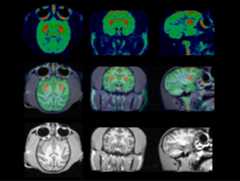

The results of the rodent brain distribution studies and ex vivo autoradiographic studies suggest that (-)-[18F]9e may be a suitable ligand for studying cholinergic innervations via the VAChT in humans. To confirm the feasibility of using (-)-[18F]9e for measuring the density of VAChT in vivo, PET imaging studies with (-)-[18F]9e were conducted in three male rhesus monkeys (Figure 5,Figure 6) on a microPET Focus 220 scanner (Concorde/CTI/Siemens Microsystems, Knoxville, TN). A representative summed image from a MicroPET study of a male rhesus macaque injected with (-)-[18F]9e demonstrated high uptake of (-)-[18F]9e in the caudate and putamen (Figure 5 upper), which is a region expressing a high density of the VAChT. These data indicate: a) (-)-[18F]9e enters the brain readily and, b) the distribution of (-)-[18F]9e is consistent with the distribution of the VAChT in brain. The tissue time-activity curves (Figure 6A) indicate that peak uptake of (-)-[18F]9e in caudate and putamen occurred at about 30 min post-i.v. injection.Figure 6B indicates that the putamen: cerebellum ratio increases with time, reaching a value of 2.1 at 2 h. These data indicate that (-)-[18F]9e is a promising and novel PET radiotracer for imaging the VAChT. Further studies will be required to determine if (-)-[18F]9e can be used in clinical imaging studies.

Figure 5.

Representative microPET (top), MRI (bottom) and co-registered images (middle). PET images are summed images (0 min to 120 min) over a 2 h dynamic scan, obtained by injection of (-)-[18F]9e into a rhesus monkey. High uptake of (-)-[18F]9e is observed in the putamen and caudate.

Acquired list mode data were histogrammed into a 3D set of sinograms and binned to the following time frames: 3×1 min, 4×2 min, 3×3 min and 20×5 min. Sinogram data was corrected for attenuation and scatter. Maximuma posteriori (MAP) reconstructions were done with 18 iterations and a beta value of 0.004. A 1.5 mm Gaussian filter was applied to smooth each MAP reconstructed image. These images were then coregistered with MRI images to accurately identify the regions of interest with Amira software (Visage Imaging, Inc., Carlsbad, CA). 3D regions of interest were manually drawn through all planes of co-registered MRI images for the caudate, putamen and cerebellum (Figure 5). The regions of interest were then overlaid on all reconstructed PET images to obtain time–activity curves. Activity measures were standardized to body weight and dose of radioactivity injected to yield standardized uptake value (SUV) (Figure 6A).